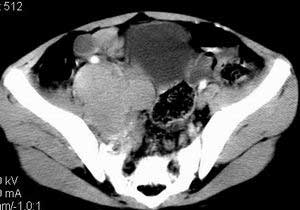

| 患者,男,9岁,因右下腹包块入院,血象不高,不规则发热,常超40度。 平扫: ![]() ![]() ![]() ![]() ![]() ![]() ![]() ![]() ![]() ![]() ![]() ![]() ![]() ![]() ![]() ![]() ![]() ![]() 增强: ![]() ![]() ![]() ![]() ![]() ![]() ![]() ![]() ![]() ![]() ![]() ![]() ![]() ![]() jiajie发言:骶椎右前区不规则软组织肿块,边缘光整,密度均匀,增强后均匀强化,右腹股沟区可见肿大淋巴结,临床有时发热,考虑淋巴瘤,儿童盆腔肿瘤应与神经母细胞瘤和横纹肌肉瘤鉴别。 longzhanghui发言:印象:盆腔右后壁不规则软组织肿块,并向前延伸.似为多个肿块融合,呈中等强化.初步考虑淋巴瘤. 听蝉观竹发言:右侧髂内、外组淋巴结肿大,从其形态和融合的情况看,同意大家意见-----考虑恶性病变,但是9岁男孩还要注意检查睾丸情况,有无隐睾? 常常类似情况是隐睾发生精原细胞瘤淋巴结转移,这个病例也要注意这一点!!! 广东凌发言:大家好,在这里我想说一下个人观点,我建议上传图片的同志能否辛苦一点就是把病史和图片都上传完整一点,比如这个病人的腹膜窗,并且这个病人的肠道的准备也是不怎么好,就从现有的质料看:病灶属于淋巴结肿大当无大的争议,有融合趋势,其内无坏死,边缘强化为主,故考虑:淋巴瘤!建议用腹膜窗看一下和肠道的关系! 阿圣发言:病灶属于淋巴结肿大当无大的争议,有融合趋势,其内无坏死,边缘强化为主,故考虑:淋巴瘤 结果是:淋巴瘤 病例来源:ct762。由宁静致远发布: http://www.radinet.com.cn/forum_view.asp?forum_id=4&view_id=2182 |